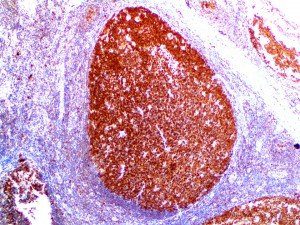

It is the ICU physician who is most likely to witness one of the deadliest manifestations of the abnormal immunological response, the cytokine storm syndrome (CSS). This response is also referred to by some as the cytokine release syndrome (CRS). CSS is characterized by continuous activation and expansion of macrophage and lymphocyte populations, which secrete large amounts of cytokines, causing the cytokine storm. This massive cytokine release is akin to hemophagocytic lymphohistiocytosis (HLH) disease, a syndrome characterized by initial unchecked and persistent activation of cytotoxic T lymphocytes and NK cells.

Clinical and laboratory manifestations of HLH include fever, enlarged liver and/or spleen, neurologic dysfunction, coagulopathy, liver dysfunction, cytopenias (i.e., low levels of erythrocytes, leukocytes, and/or platelets), hypertriglyceridemia, hyperferritinemia, hemophagocytosis, and eventually diminished NK cell activity as the immune system becomes progressively paralyzed. HLH can be familial (primary HLH) or secondary to another disease process (sHLH), such as rheumatic disease, in which it is referred to as macrophage activation syndrome (MAS, characterized by elevated ferritin).